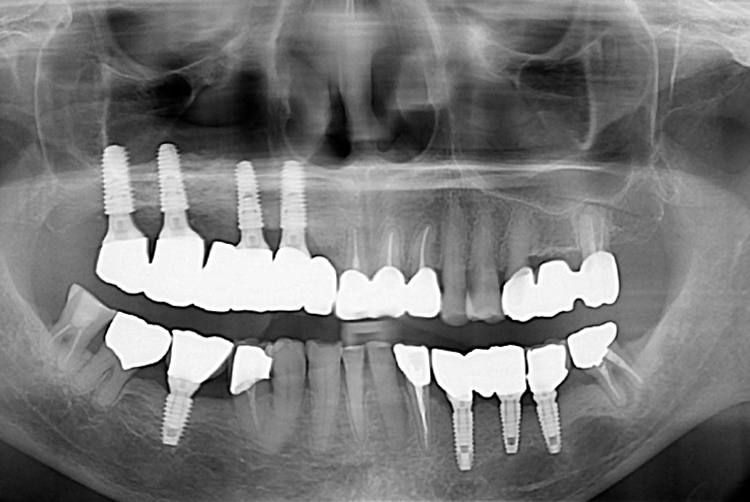

치료후 : 2017-03-17

세종치과는 많은 환자와 다양한 케이스를 바탕으로 항상 편안한 임플란트 수술을 제공하고자 노력하고,

오래동안 튼튼히 쓸 수 있는 임플란트 수술을 가장 큰 목표로 삼고 있습니다